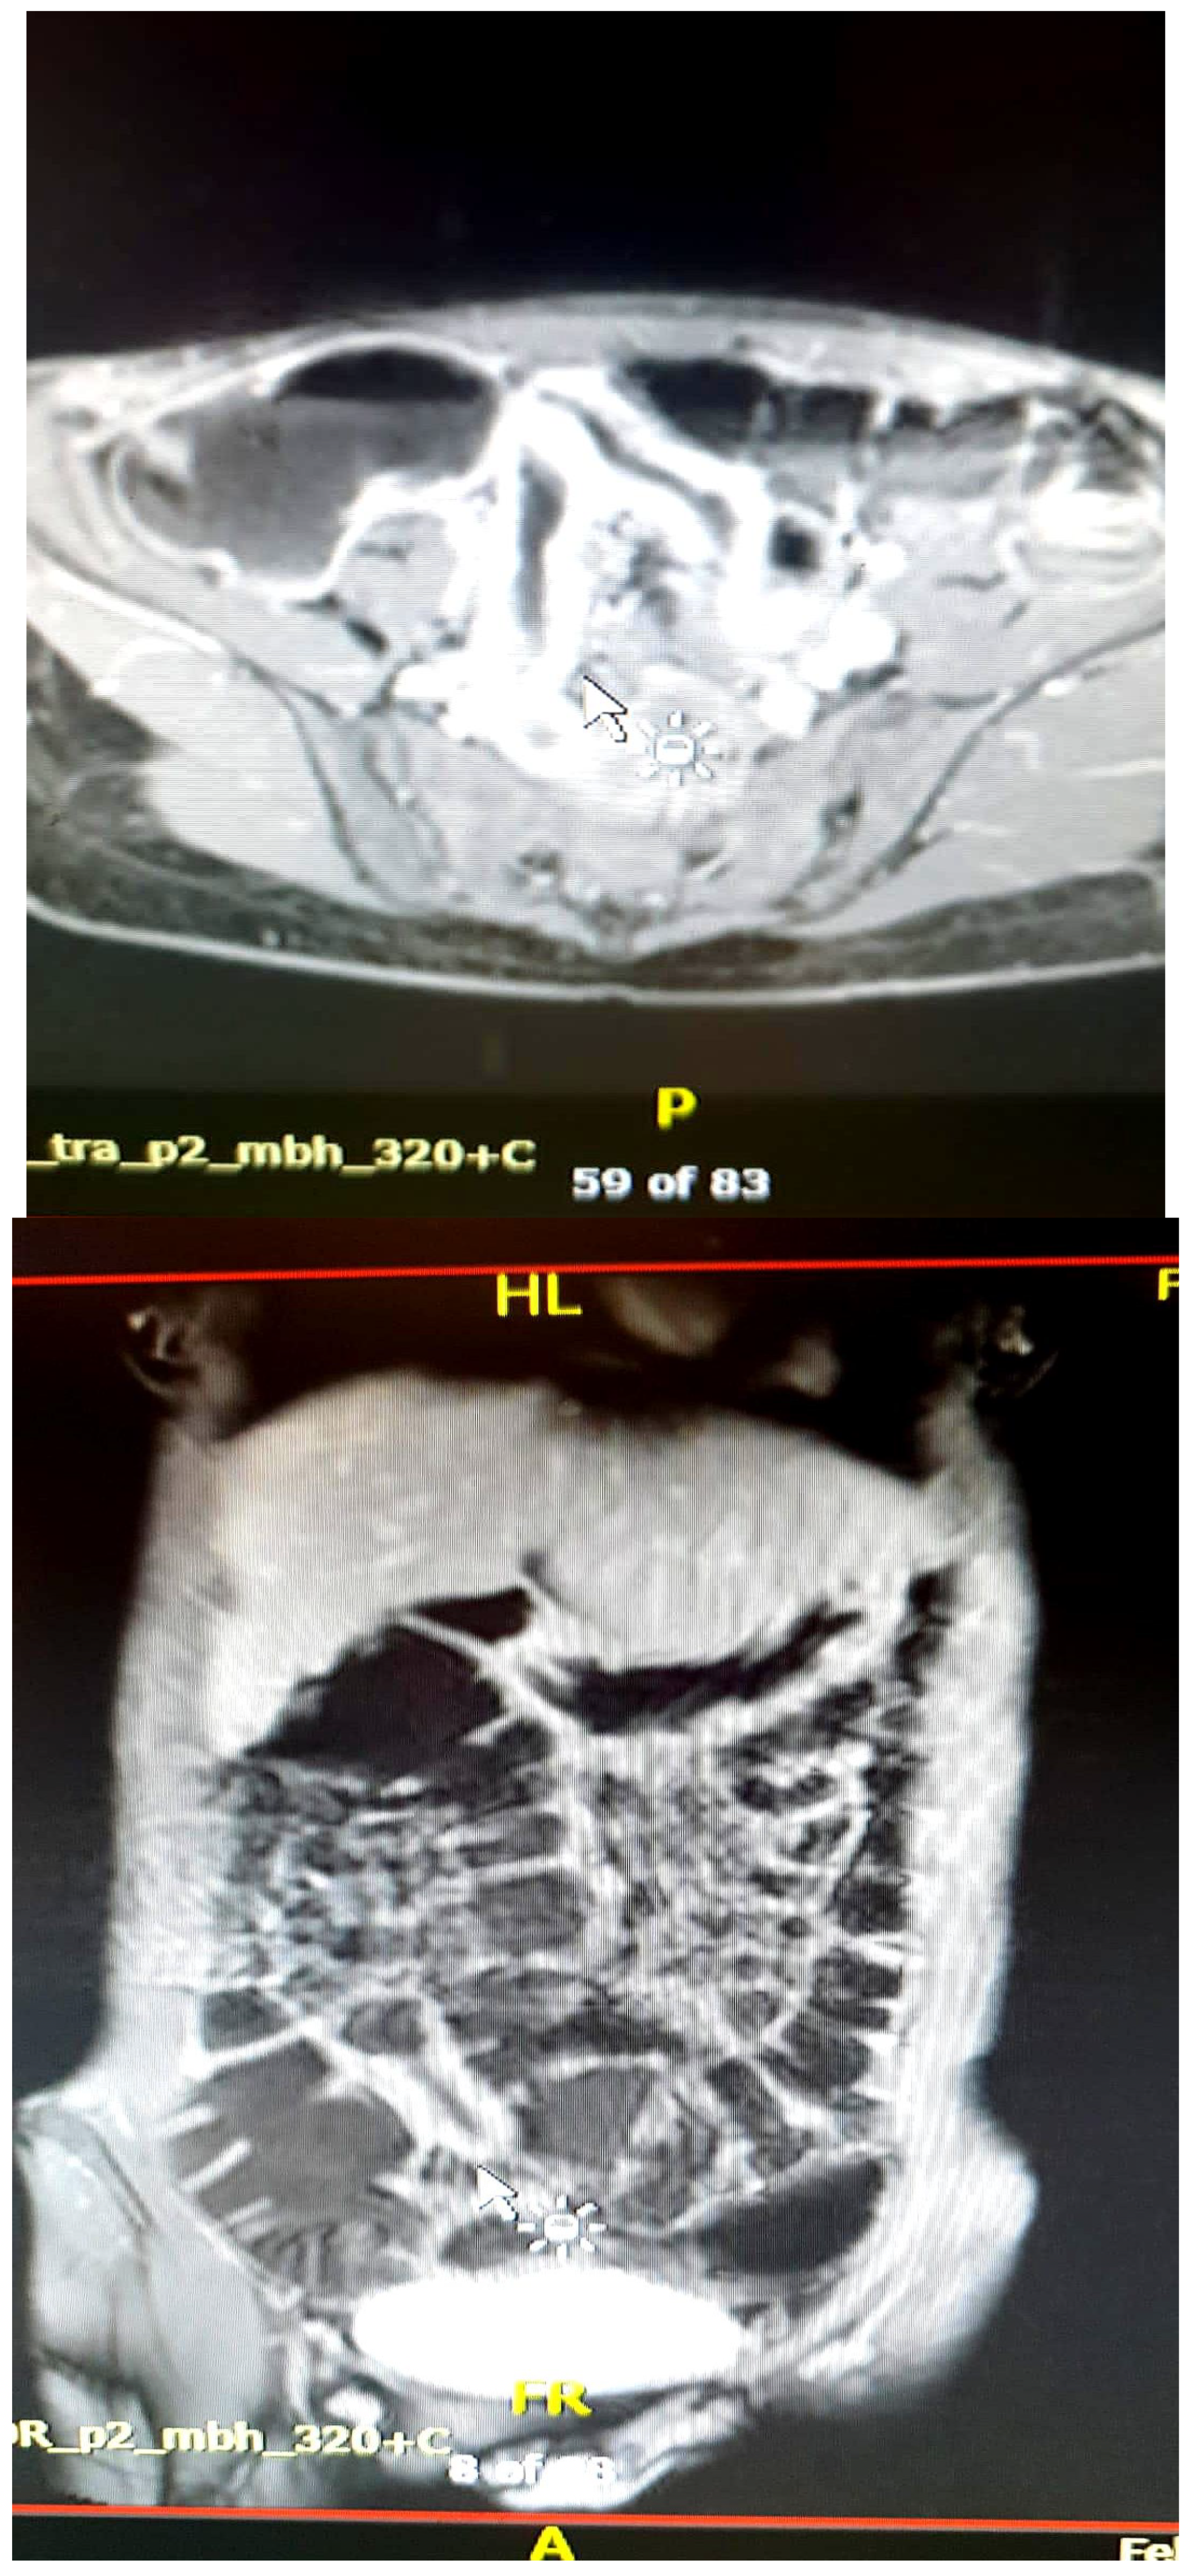

- Magnetic Resonance Enterography (MRE) is essential in the evaluation of inflammatory bowel disease, providing simultaneously detailed images of the intestinal wall and adjacent structures and inflammatory lesions [22], differentiating inflammation from fibrosis in both the small and large intestine submucosa and the perineal area [34,35]. MRE also has high accuracy in staging small bowel inflammatory bowel disease [29], in monitoring treatment response and relapse [22], and in detecting and classifying isolated forms of colonic involvement [36]. This imaging modality is preferred in complex cases with evidence of penetrating, fistulizing, and stenosing lesions [22], as well as in fistulas and perianal sepsis [13]. Fat smudging, fecal sign, fluid level, gaseous distension, comb sign (related vascular congestion), and lymphadenopathy are the elements mainly visualized/detected by MRE [2]. Another advantage—perhaps the most important—is that MRE is the safest and most cost-effective cross-sectional imaging method that can be used to evaluate the activity of Crohn’s disease and ulcerative colitis in both adults and young people [37], without the use of ionizing radiation [2]. Taylor et al. have shown that MRE has a sensitivity of 97% for detecting inflammatory bowel diseases, over 90% for fibro-inflammatory strictures, and specificity of over 95% [29].

- Restricted diffusion

- DWI hypersignal + low ADC in acute inflammation.

4.1. Differentiating Between Active Inflammation and Fibrosis

4.2. Screening/Detection of Complications